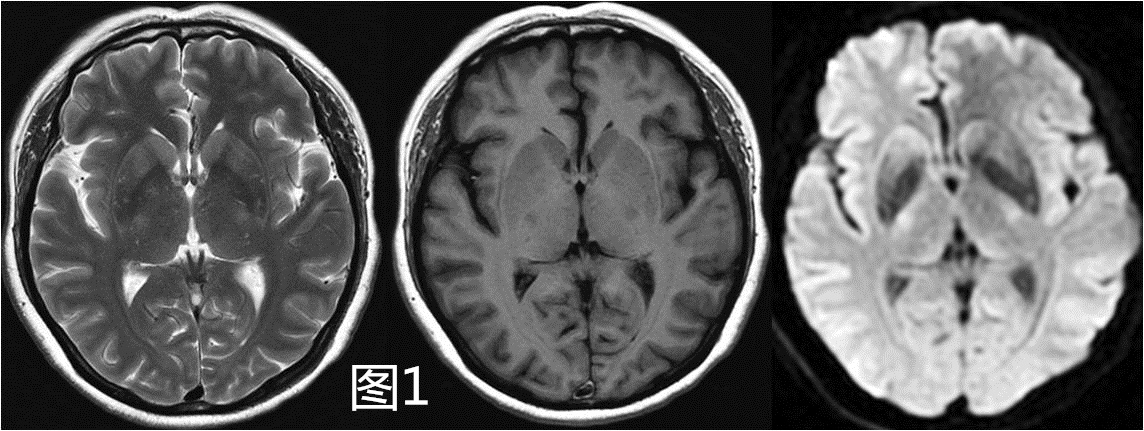

图1 头部MR平扫(T1WI、T2WI、DWI)

例如,某位女性患者,48岁,经常头晕。常规MRI平扫序列(如图1所示),未见异常信号改变。而在3D ASL脑灌注检查后,则可以发现右侧大脑中动脉供血区大片低灌注区。虽然TOF MRA(图2C)序列可以帮助发现大血管狭窄或闭塞,但仅仅停留在形态学上的诊断。因为对于同样的大血管病变,因个体代偿能力不同其预后和治疗后风险也不同,因此进一步的灌注水平的评估极为重要。